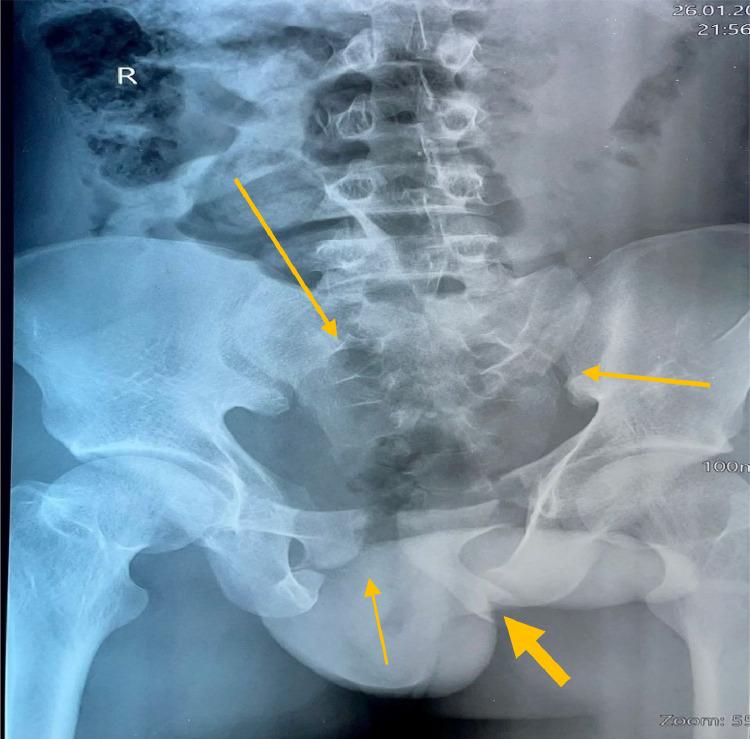

Pelvic fractures can range from simple, requiring almost no therapy, to complex, mandating the attention of the orthopedic surgeon, trauma surgeon, interventional radiologist, or other specialists because they are associated with multisystem injury and life-threatening hypotension. We present a 16-year-old male who presented with a complex pelvic fracture following a motor vehicle accidents that did not survive despite the efforts in resuscitation. In complex pelvic fracture with hemodynamic instability (hypotension persevered) and high index suspicion of bladder injury, there is an immediate need for operative intervention, regardless of negative/positive FAST (Focused Assessment with Sonography in Trauma).

骨盆骨折的严重程度差异很大,从几乎无需治疗的简单骨折到复杂骨折,后者因与多系统损伤及危及生命的低血压相关,需要骨科医生、创伤外科医生、介入放射科医生或其他专科医生的关注。我们报告一例16岁男性患者,其在机动车事故后出现复杂骨盆骨折,尽管进行了复苏努力,但仍未存活。对于伴有血流动力学不稳定(持续低血压)且高度怀疑膀胱损伤的复杂骨盆骨折,无论创伤超声重点评估(FAST)结果为阴性或阳性,都急需进行手术干预。